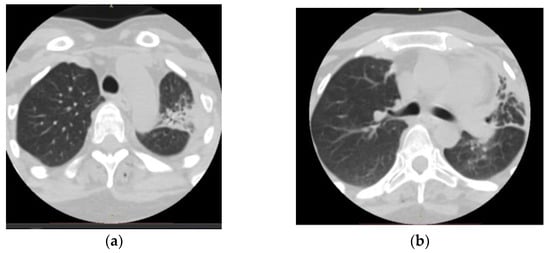

- Radiological evidence of chronic pulmonary lesion;

- Mycological demonstration of Aspergillus fumigates hyphae by microscopy from spu-tum, microscopy and culture from bronchial aspirate, and histopathological evi-dence of the presence of Aspergillus fumigates hyphae with dichotomous branching in the spinal cord biopsy;